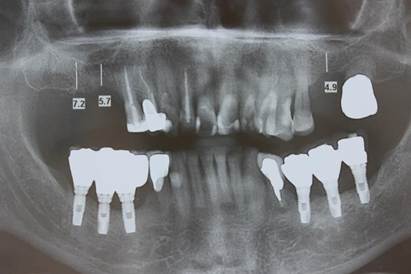

Paciente A. R. S, gênero feminino, 67 anos de idade, compareceu ao consultório particular, em 2020, com a queixa de mobilidade na região dos implantes inferiores. Na anamnese, paciente realizava acompanhamento médico devido ao quadro de diabetes mellitus, com uso de medicamentos específicos. Ao exame clínico, verificado mobilidade acentuada na regão do 36, 37, 46 e 47. Foram solicitados radiografia panorâmica (Figura 04. A) e tomografia computadorizada da área, evidenciando comprometimento periodontal avançado nas reabilitações com implantes dentários. O plano de tratamento proposto foi a remoção dos implantes e nova reabilitação da região atrófica.

Figura 04. A) Radiografia panorâmica inicial. B) Implantes dentários removidos – região do 36, 37, 46 e 47.

Figura 07. A – D) Aspecto final. E) Radiografia panorâmica final.